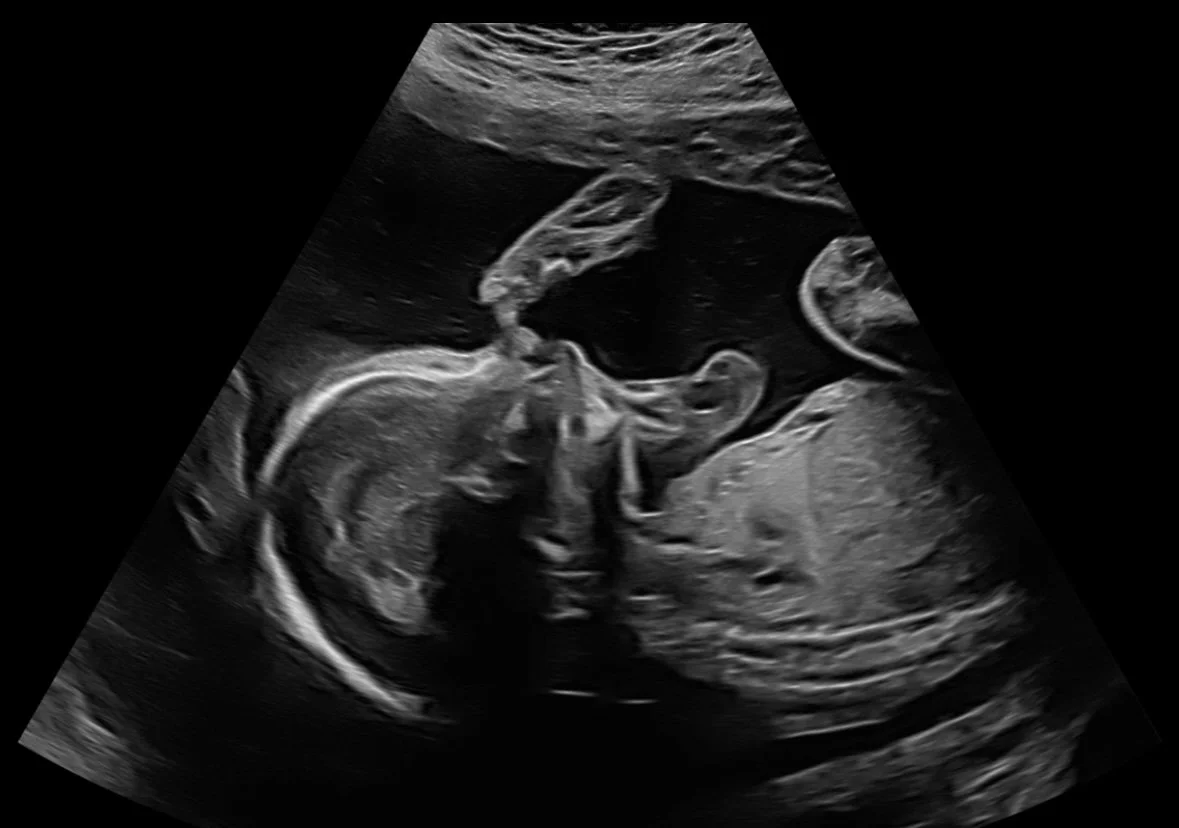

Bonding with Baby P